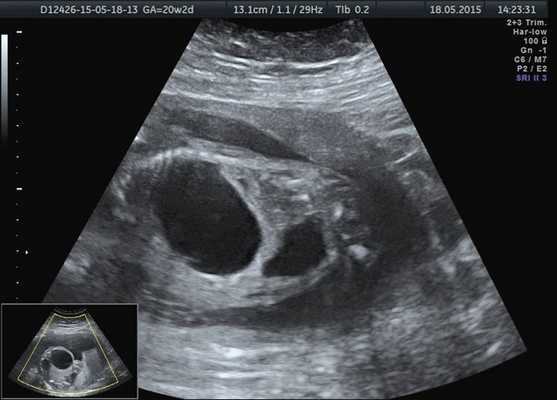

Область правой почки занимало округлое тонкостенное анэхогенное образование до 36 мм в диаметре. Правая почка была уменьшена в размерах до 17×9×20 мм, смещена и располагалась, распластываясь в виде полумесяца по задней поверхности образования (рис. 4). Правый мочеточник не визуализировался. Паренхима обеих почек была повышенной эхогенности, кортикомедуллярная дифференцировка почечных слоев нечеткая.

Рис. 4. Образование возле правой почки и расширенный мочевой пузырь плода.

Надпочечники с обеих сторон были интактны. Мочевой пузырь был увеличен до 20 мм в диаметре, с утолщенными стенками и в процессе динамического осмотра не опорожнялся (рис. 5). Изменений по остальным органам и системам не было выявлено.

Рис. 5. Расширенный мочевой пузырь плода.